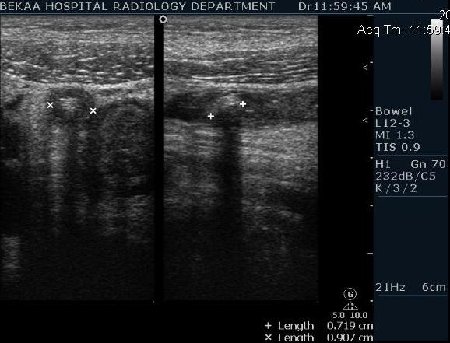

Диагностика острого аппендицита по УЗИ: очень актуальная тема; УЗ аппараты практически есть во всех клиниках; метод доступный и не сложный; главное владеть правильной техникой. Не буду загружать лишней теорией и разными ссылками; поделюсь практическим опытом. У меня линейный датчик 3-12 мегагерц с плавающей частотой; аппарат Филипс HD 11, всегда включаю соно-КТ (9800 цифровых каналов) и гармонику когда смотрю кишечник. Нормальный аппендикс видеть можно; но вопрос зачем??? Как правило, если при наличии достаточного опыта аппендикс не виден; значит скорей всего аппендицита нет. Когда "идешь" на аппендицит то главное по началу набраться терпения и......хорошая компрессия! По началу надо минут 10-15; потом когда появится достаточный опыт; за 2-5 минут можно справится и получить отличную визуализацию. Мочевой пузырь лучше опорожнить; часто он приподнимают тонкий кишечник и может закрыть "окно" через которое будет видно апендикс. Сначала находим слепую кишку потом находим илео-цекальное соединение;

после начинаем производить хорошую компрессию датчиком попрося пациента сообщить в какой точке боль наиболее выражена; медленными движениями датчика сканируем область наибольших болевых ощущений и как правило находим утолщенный отросток. Лучше начинать с поперечной визуализации и идти к верхушке аппендикса что бы убедится что это аппендикс и он заканчивается, а не тонкая кишка (которая если и закончится то только переходя в слепую); потом надо аккуратно развернуть продольно датчик и посмотреть от верхушки аппендикса к слепой. Норма диаметра: 3-4 мм; 5-6 мм под вопросом (клиника решает; но я в катаральный аппендицит не верю); 7-8 мм и больше, не компремируемый (фиксированный отросток)-острый аппендицит! Помимо наличие утолщенного аппендикса; признака "бычьего глаза" (bull-eye sign) при поперечном сканировании; надо обращать внимание на присуствие аппендоколитов в просвете; деструкцию стенки и свободной жидкости в зоне интереса.